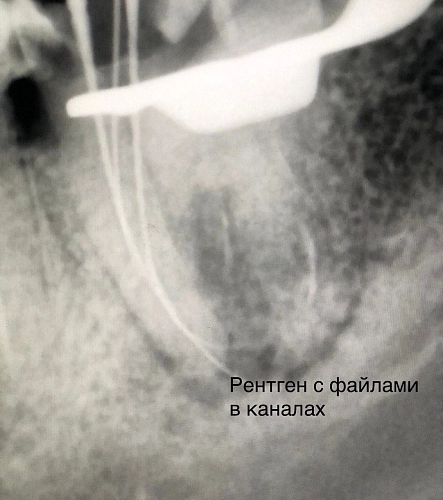

На диагностическом рентгеновском снимке был обнаружен очаг деструкции костной ткани в области данного зуба, так же не полностью запломбированные каналы и отломок инструмента в одном из корневых каналов.

Для того чтобы купировать боль и вылечить зуб необходимо было извлечь отломок, перелечить все корневые каналы и запломбировать их новым пломбировочным материалом. Доктор успешно провел процедуру и таким образом спас зуб от удаления